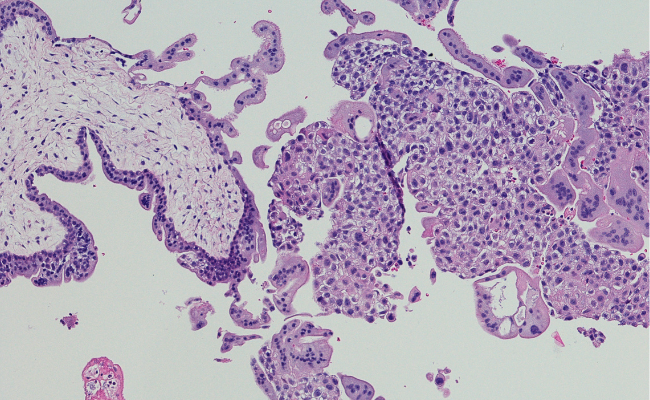

The diagnostic journey for trophoblastic neoplasia is a multifaceted process that integrates clinical evaluation, imaging studies, and laboratory tests. Clinical symptoms, including vaginal bleeding, an enlarged uterus, and elevated levels of human chorionic gonadotropin (hCG), act as crucial indicators triggering further investigation. Ultrasonography emerges as a primary imaging modality, facilitating the assessment of tumor extent and identification of abnormalities. Concurrently, monitoring hCG levels proves instrumental in tracking treatment response and detecting potential recurrences. Histopathological examination of tissue samples, obtained through methods such as biopsy or dilatation and curettage (D&C), stands indispensable for confirming the diagnosis and determining the specific type of trophoblastic neoplasia. Molecular testing, including DNA ploidy analysis, provides additional insights that guide treatment decisions. Trophoblastic neoplasia refers to a group of rare tumors that arise from abnormal proliferation of trophoblastic cells, which are cells that surround a fertilized egg and help form the placenta.

7. Tissue Biopsy: In cases where a tumor is suspected, a biopsy of the tissue may be performed to confirm the diagnosis and identify the specific type of trophoblastic neoplasia.